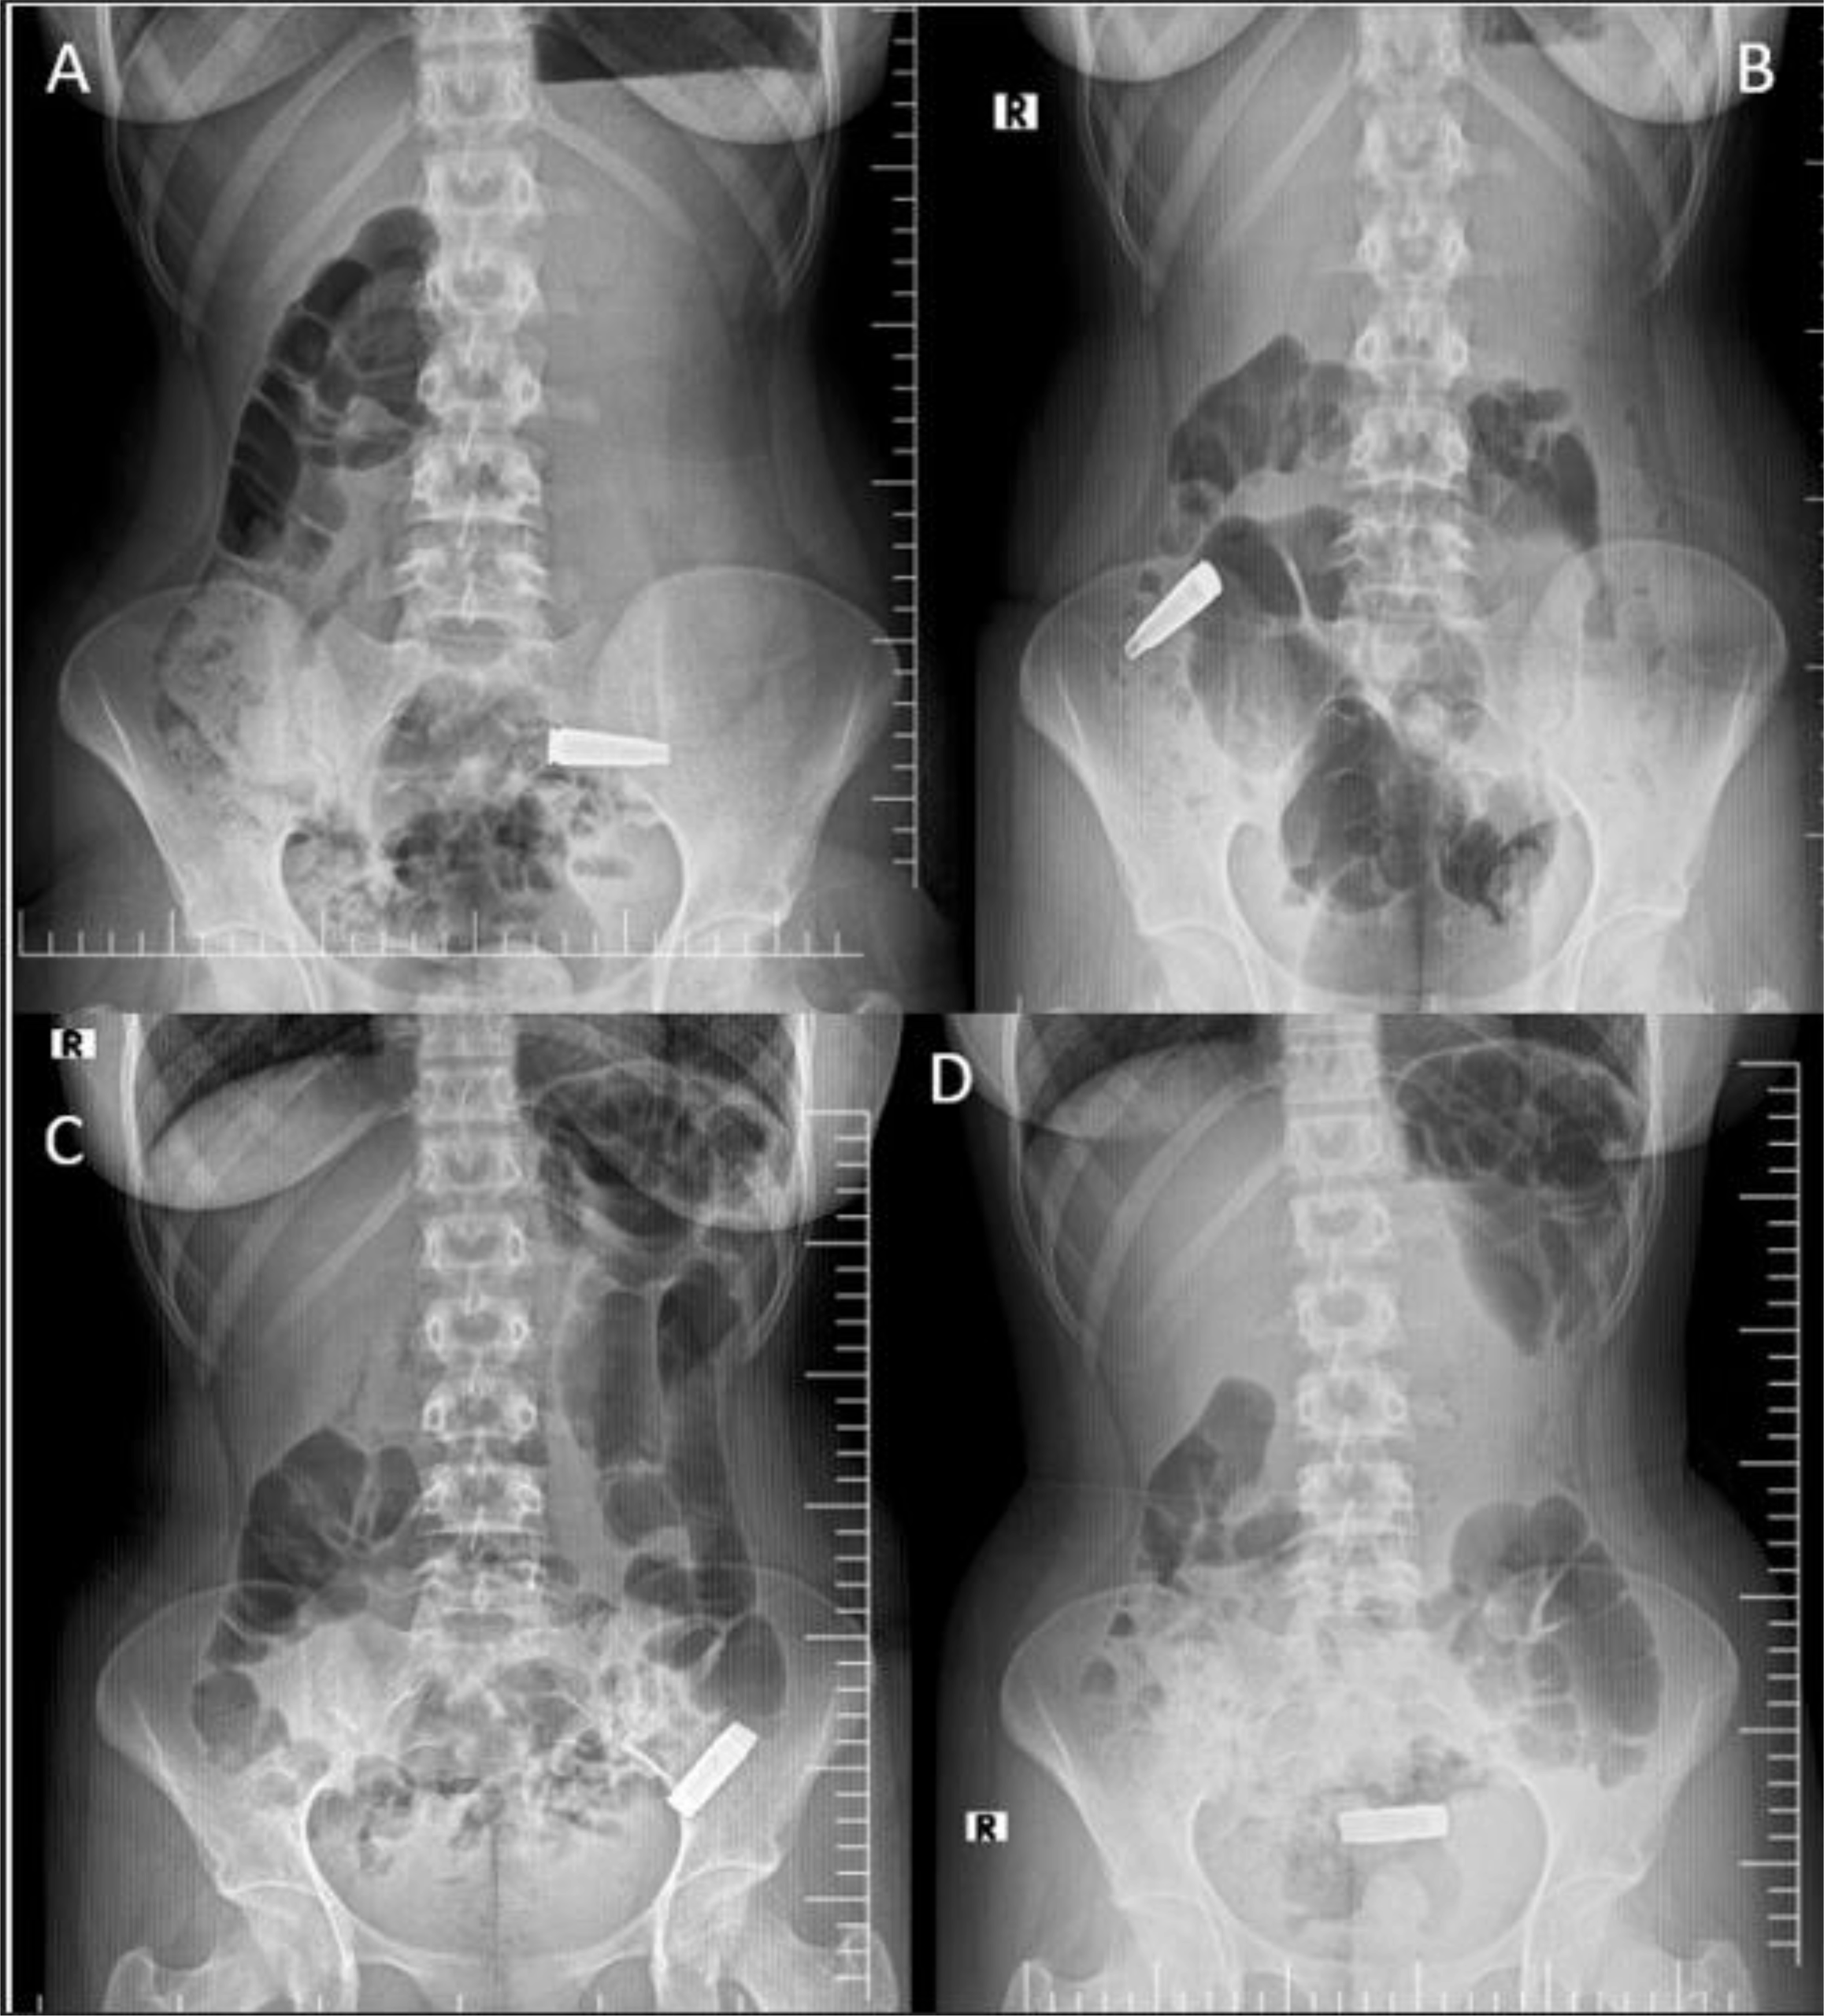

Spontaneous passage of an accidentally ingested metallic bullet casing in an adolescent: a case report | International Journal of Emergency Medicine

Foreign body ingestion is a relatively common clinical problem that can occasionally be life-threatening [1]. In the United States, approximately 120,000 cases are reported annually, most of which occur in children between 6 months and 3 years of…